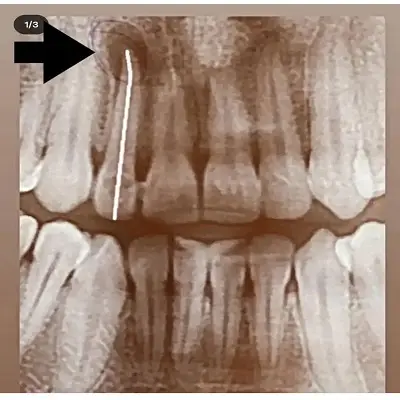

بهترین دکتر درمان ریشه در شهریار خدمات تخصصی عصبکشی را با هدف حفظ دندان طبیعی و کاهش درد بیماران ارائه میدهد. تشخیص دقیق عفونت ریشه با استفاده از تصویربرداری پیشرفته، باعث میشود درمان با دقت بالا و ماندگاری بیشتر انجام شود.

درمان ریشه دندانهای تککاناله و چندکاناله، درمان مجدد ریشههای عفونی و کنترل دردهای شدید دندانی از مهمترین خدمات متخصص درمان ریشه در شهریار است. این خدمات بهگونهای انجام میشوند که از گسترش عفونت و نیاز به کشیدن دندان جلوگیری شود.